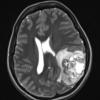

NEOPLASMS (GLIAL)

Pleomorphic Xanthoastrocytoma (PXA) (14)